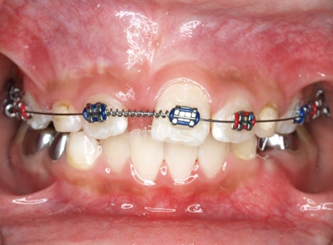

Răng thừa (a) làm R11 (b) bị kẹt không mọc ra được Tạo khoảng trước phẫu thuật

Phẫu thuật lấy răng thừa sau 4 tháng tạo khoảng Chỉnh nha kéo R11 ngầm lên

Qúa trình chỉnh nha kéo răng cửa mọc ngầm hoàn tất

Hình 5: Minh họa phẫu thuật lấy răng thừa kết hợp với chỉnh nha ở một bé trai 9 tuổi